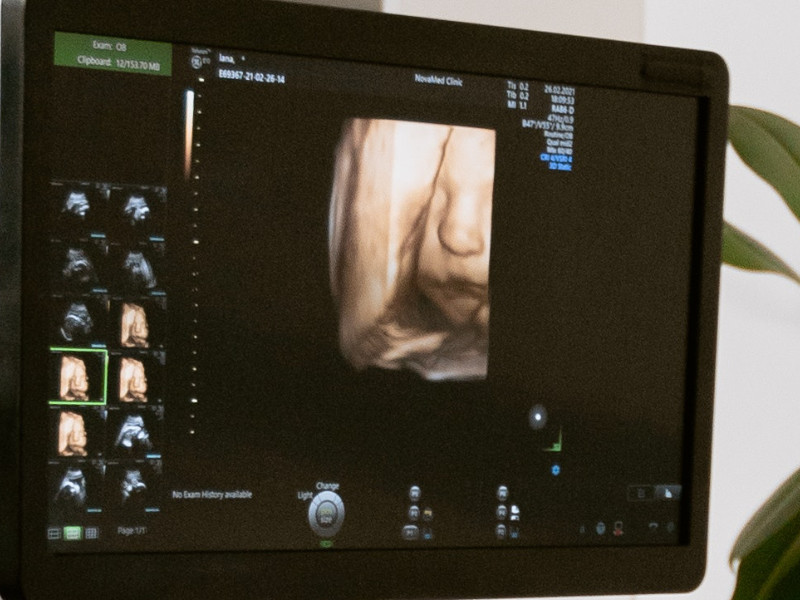

Si les conditions sont optimales, il est possible de réaliser une échographie 3D de votre bébé.